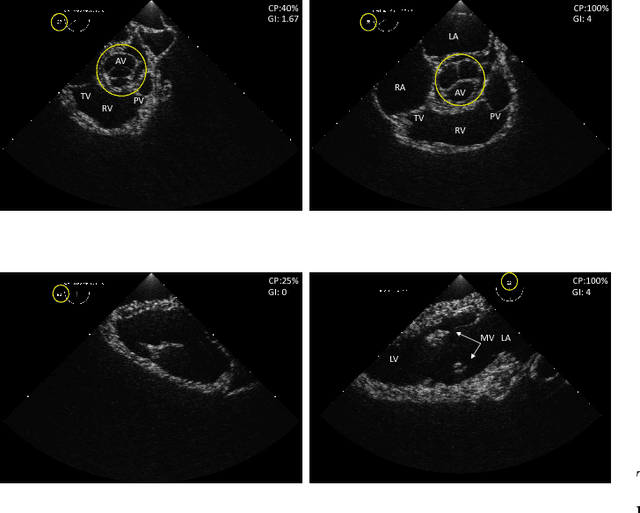

Abstract:Transoesophageal echocardiography (TEE) is a valuable diagnostic and monitoring imaging modality. Proper image acquisition is essential for diagnosis, yet current assessment techniques are solely based on manual expert review. This paper presents a supervised deep learn ing framework for automatically evaluating and grading the quality of TEE images. To obtain the necessary dataset, 38 participants of varied experience performed TEE exams with a high-fidelity virtual reality (VR) platform. Two Convolutional Neural Network (CNN) architectures, AlexNet and VGG, structured to perform regression, were finetuned and validated on manually graded images from three evaluators. Two different scoring strategies, a criteria-based percentage and an overall general impression, were used. The developed CNN models estimate the average score with a root mean square accuracy ranging between 84%-93%, indicating the ability to replicate expert valuation. Proposed strategies for automated TEE assessment can have a significant impact on the training process of new TEE operators, providing direct feedback and facilitating the development of the necessary dexterous skills.